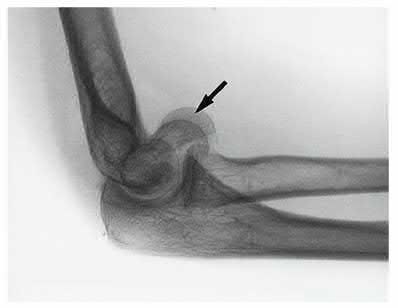

A 72-year-old woman falls down stairs and sustains the injury shown in Figure A. Additional radiographs are performed in Figure B to help assess the fracture pattern. These additional radiographs represent which of the following?

Additional traction radiographs are performed in distal humerus fractures to better understand the fracture configuration.

Traction radiographs help align the fracture fragments for better visualization. This is useful in comminuted fractures where distal fragments are telescoped or flexed on the proximal fragments, making CT scan visualization difficult.

Proper visualization can help determine (1) the approach to the distal humerus, (2) whether to perform ORIF or total elbow arthroplasty (in select patients), (3) whether to add a 3rd plate (lateral column), (4) whether to add tricortical bone graft to augment distal fixation and restore trochlear width.

Figures A and B show a distal humerus fracture without traction (A) and with traction (B) applied. Illustration A shows the same fracture after bicolumnar plating. Illustration B shows the different surgical approaches to the distal humerus (A, Campbell triceps splitting; B, O'Driscoll triceps reflecting anconeus pedicle [TRAP]; C, Bryan-Morrey triceps reflecting; D, olecranon osteotomy)